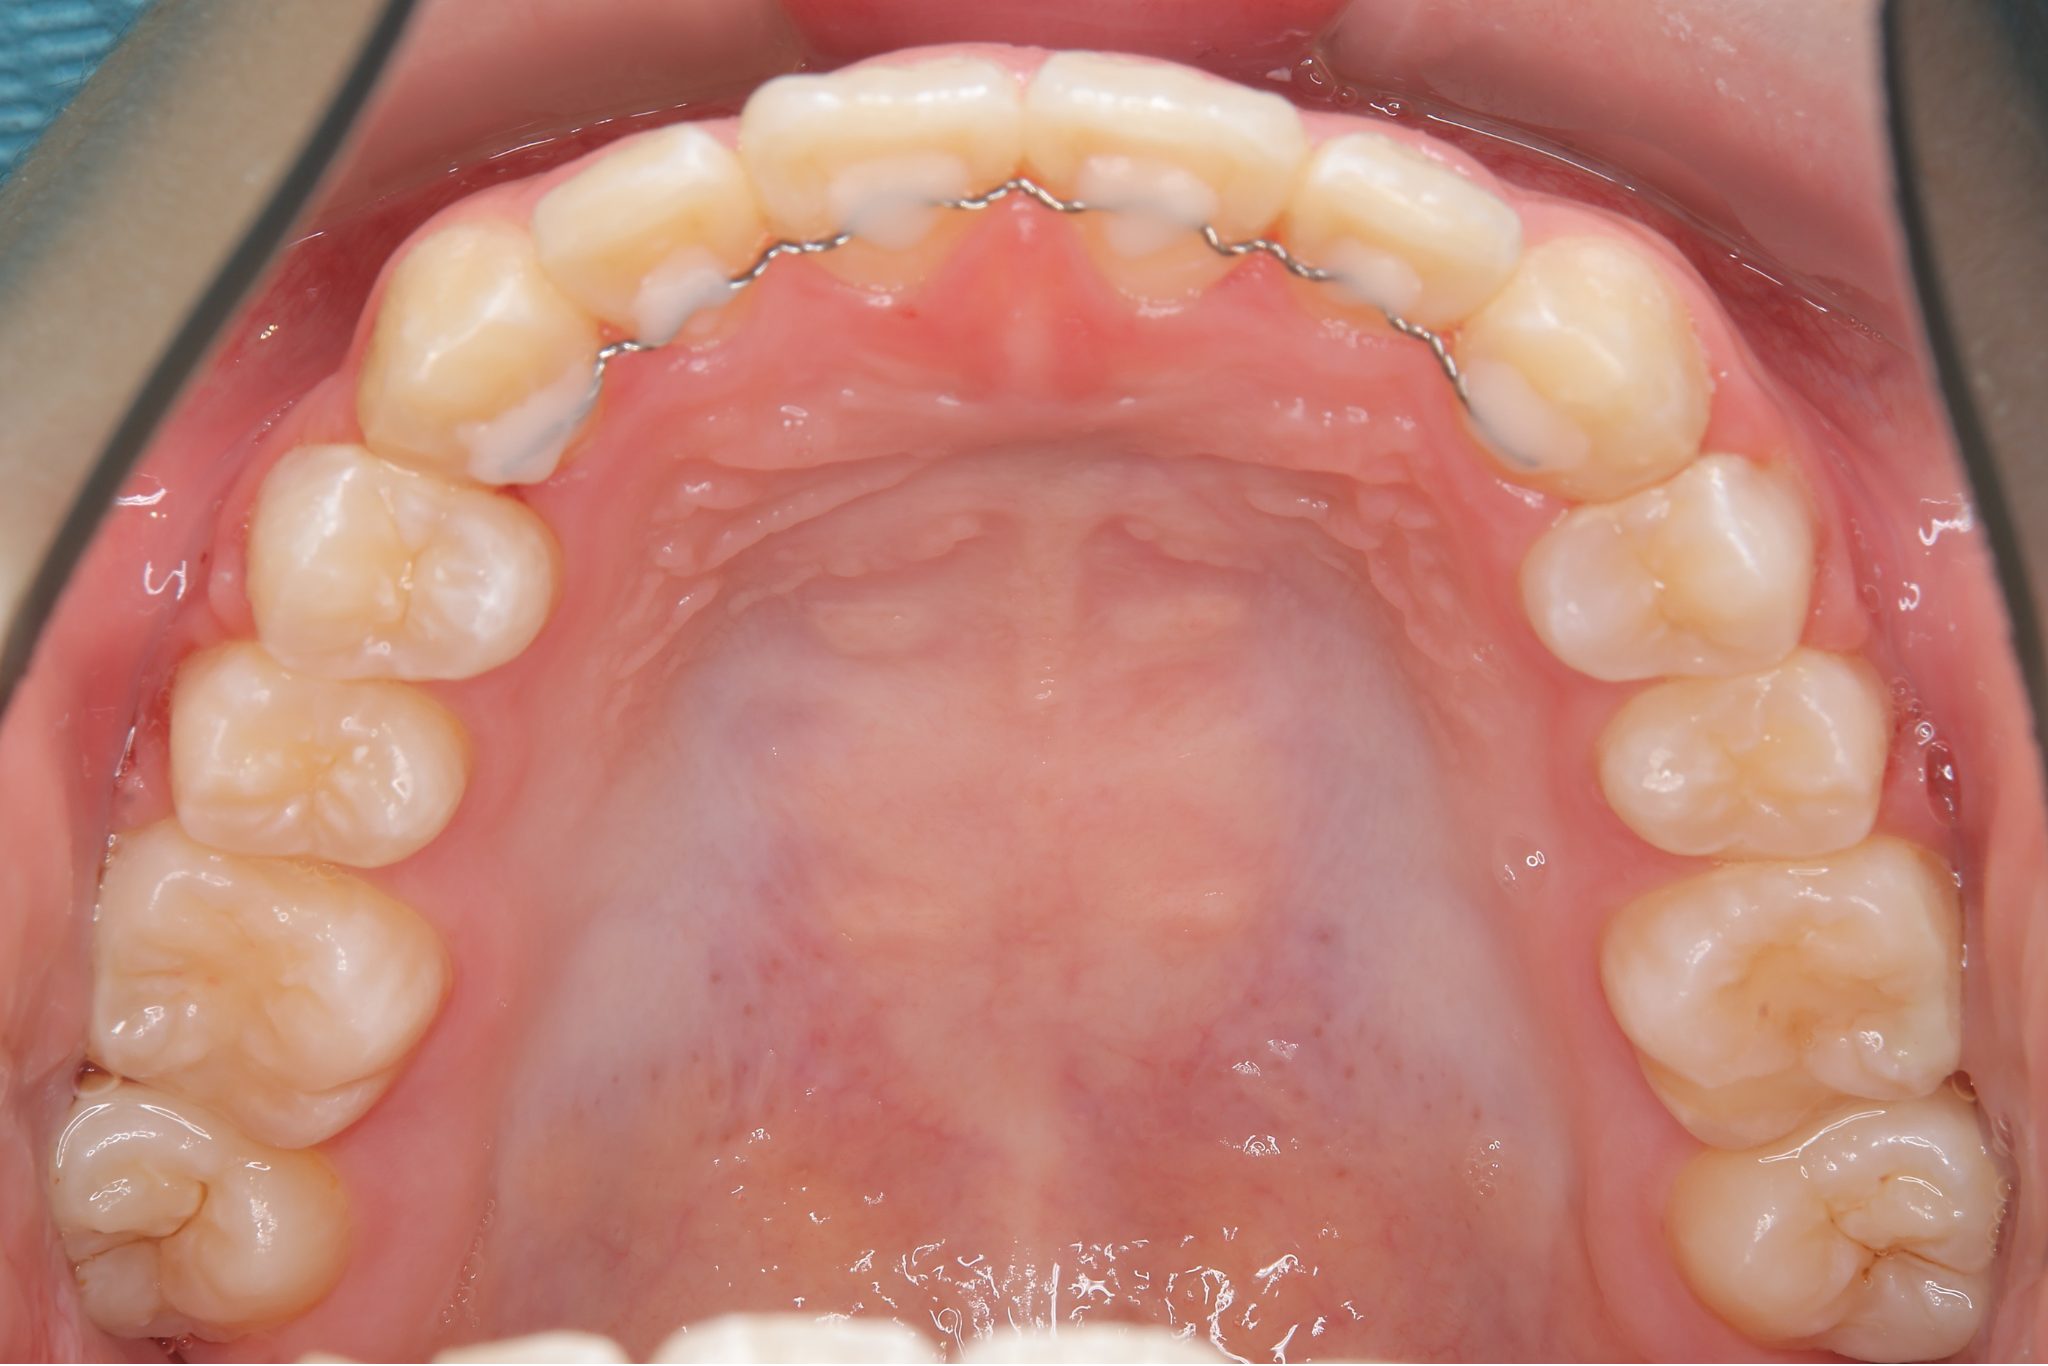

アフター

全顎ワイヤー矯正 症例_805